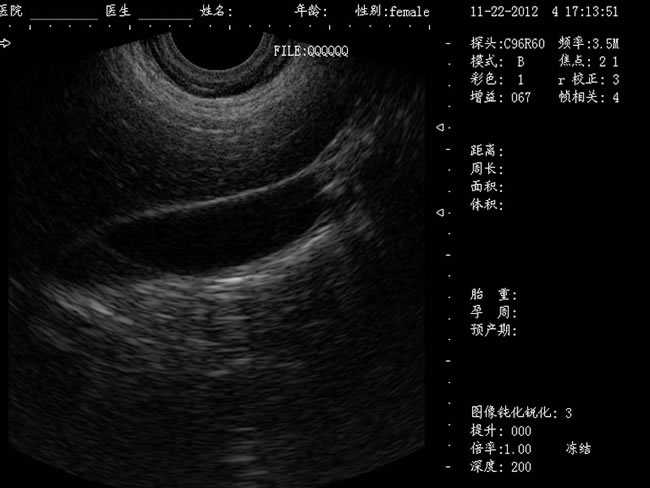

定位精確 手術(shù)效率高:實(shí)時(shí)動(dòng)態(tài)頻率掃描等全數(shù)字超聲成像技術(shù)、生成精確的圖像引導(dǎo)手術(shù)器械迅速到大手術(shù)位置,避免損傷子宮內(nèi)膜和子宮穿孔的現(xiàn)象,即減輕了患者的痛苦又極大提高了手術(shù)效率。

高密度全數(shù)字波束形成:采用全新一代混頻技術(shù)、數(shù)字嵌入系統(tǒng)及數(shù)字整序技術(shù)

有效提升系統(tǒng)的穩(wěn)定性、可靠性:實(shí)時(shí)動(dòng)態(tài)孔徑成像,充分保證圖像的精度和清晰度

CXA10R/6.5MHz 腔內(nèi)探頭

選配:CXA60R/3.5MHz 凸陣探頭

隨著醫(yī)療技術(shù)水平的提高,目前婦產(chǎn)科手術(shù)中所應(yīng)用的相關(guān)設(shè)備也有了加大的改進(jìn)。尤其是在人工流產(chǎn)手術(shù)中,將B超婦產(chǎn)科手術(shù)監(jiān)視儀應(yīng)用到手術(shù)過程中,彌補(bǔ)傳統(tǒng)手術(shù)中所采用設(shè)備的不足之處,減輕手術(shù)中患者的疼痛感覺,使得手術(shù)順利的完成。這種儀器相比于傳統(tǒng)的儀器來說,其在操作上更為方便和簡單,能夠?qū)θ焉锓磻?yīng)有很好的療效。